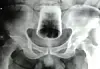

En 47-årig mand fra Nepal fik lægerne på det lokale hospital til at spærre øjnene op.  For da lægerne tog et røntgenfotografi af mandens mave, dukkede et helt drikkeglas op på billedet.

Glasset sad godt og grundigt fast i numsen.

Den forpinte patient gik til bekendelse og forklarede ifølge Journal of Nepal Medical Association, at han i fuldskab havde stukket glasset op i numsen.